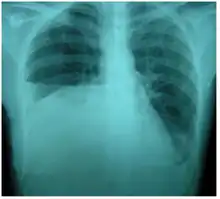

| Right sided pleural effusion caused by urinothorax | |

Urinothorax (pl. urinothoraces) is defined as urine in the fluid-filled cavity that surrounds the lungs.[1] It is usually caused by obstructive uropathy. It is mainly diagnosed by analyzing the pleural fluid. Treatment involves treating the underlying condition, which typically results in resolution of the urinothorax. It is an extremely rare cause of pleural effusion.[2]

The characteristics of people affected by urinothorax are poorly defined. Urological symptoms tend to occur, while the respiratory symptoms are typically nonexistent or mild.[3] Difficulty breathing, occurring in moderate to large pleural effusions, is the most common respiratory symptom.[4] Other symptoms include fever, abdominal pain, chest pain, and reduced urination.[3] It typically occurs within hours of the causative condition.[5]